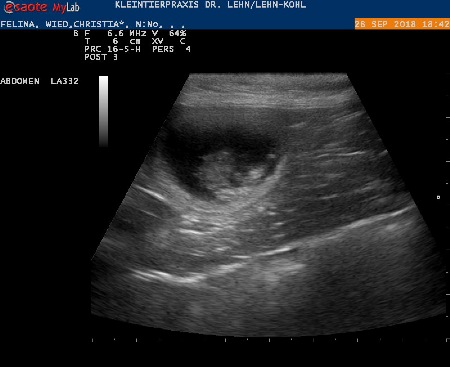

28.09.18 :

Wir waren beim Ultraschall ...Felina ist trächtig !!!